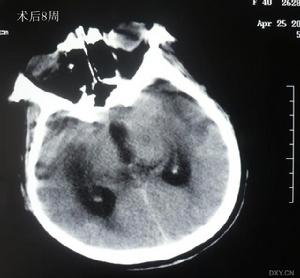

腦豬囊尾蚴病術後複查1.有局灶或彌散的腦症狀和體徵如頭痛、癲病發作、顱內壓增高、精神症狀者,並排除了其他原因所造成的腦損 害。

3.頭部CT、MRI顯示有典型的囊蟲改變。

(1)顳肌下減壓術:腦實質內多發性囊蟲因個數太多無法一一摘除,如果並發顱內壓增高危及病人生命或影響視力而又不能用藥物控制時根據情況可施行一側或雙側顳肌下減壓術。

②開顱囊蟲摘除術:對於腦室內囊蟲尤其是四腦室的囊蟲、腦實質中單發並形成占位效應的囊蟲可以採用開顱摘除摘除囊蟲時儘量將其完整取出切忌使其破裂,摘除後還要反覆沖洗。